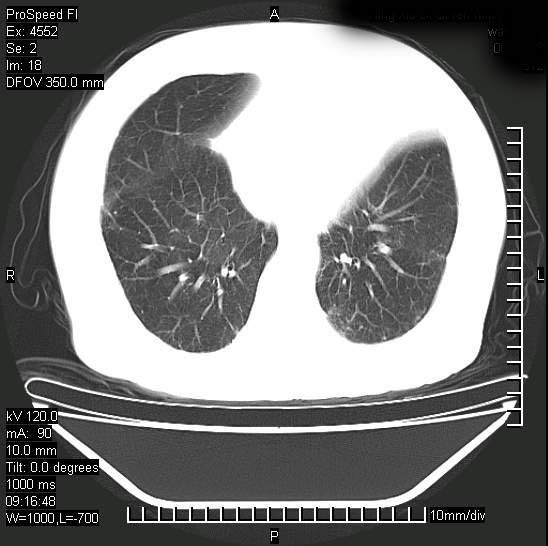

支持陈旧性肺结核并两下肺感染,两侧胸腔积液。

支持  结核ban感染,节段性肺不张,支气管内膜结核可能

继发性结核感染加重。左侧合并有支气管内膜结核。

1)两肺结核并感染。2)不排除左肺上叶中央型肺癌并阻塞性肺炎、肺不张可能;建议行纤支镜检查。3)右肺门及纵隔淋巴结肿大。4)双侧胸腔积液。

陈旧性肺结核及左下肺不张,咯血后肺部感染,双胸腔积液,高热可能与痰液引流不畅有关。